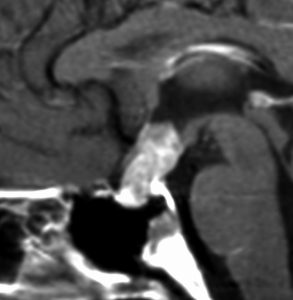

再発ジャーミノーマの画像です。延髄背側の閂 ovexという部位に再発しています。

このパターンはとても多いです。なぜかというと,全脳室照射の時に,第4脳室下端のovexの上衣 ependyum を照射野に入れない放射線治療医の先生がいるからです。放射線科の先生にもちょっとした知識が必要なのです。

これは再治療で腫瘍が消えても不可逆的な重症の延髄障害を残してしまいます。